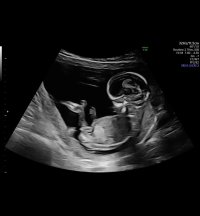

Åå, så kjedelig med dårlige bilder :/.. Jeg har dette også, men her ser man heller ikke stort. Jordmor sa ingenting om hva hun trodde eller noe som helst om kjønnet..Disse bildene var veldig dårlig til å være 14 uker. har du flere fra denne eller tidligere? burde være lett å se kjønn når man er så langt på vei. det på bilde nr 1 er ikke nub, det er en del av benet som har kommet med på bildet. Jeg tror det er jente da det ville vært veldig synlig i uke 14 om det var gutt. Ser og lang hvit strek på flere av bildene som samsvarer med jentenub.